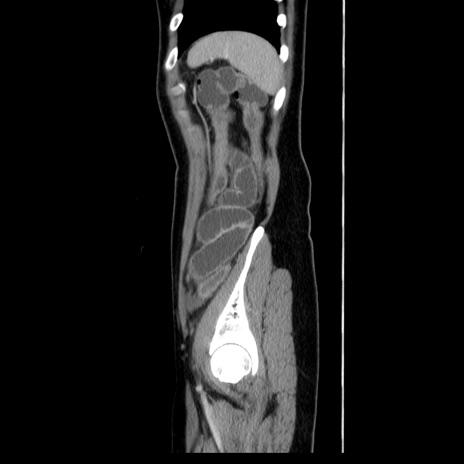

症例39(矢状断像)

【症例】40歳代女性

【主訴】上下腹部痛

【現病歴】2日目から下腹部痛あり。夜間は痛みで眠れなかった。昨日より上腹部痛と下痢が出現。臥位で痛みは軽快したため、休んでいた。本日になって臥位でも立位でも痛みが強くなってきたため救急要請。

【既往歴】子宮内膜症

【身体所見】部:平坦・軟、左上下腹部に圧痛あり、反跳痛あり。

【データ】WBC 21800、CRP 26.78

CT